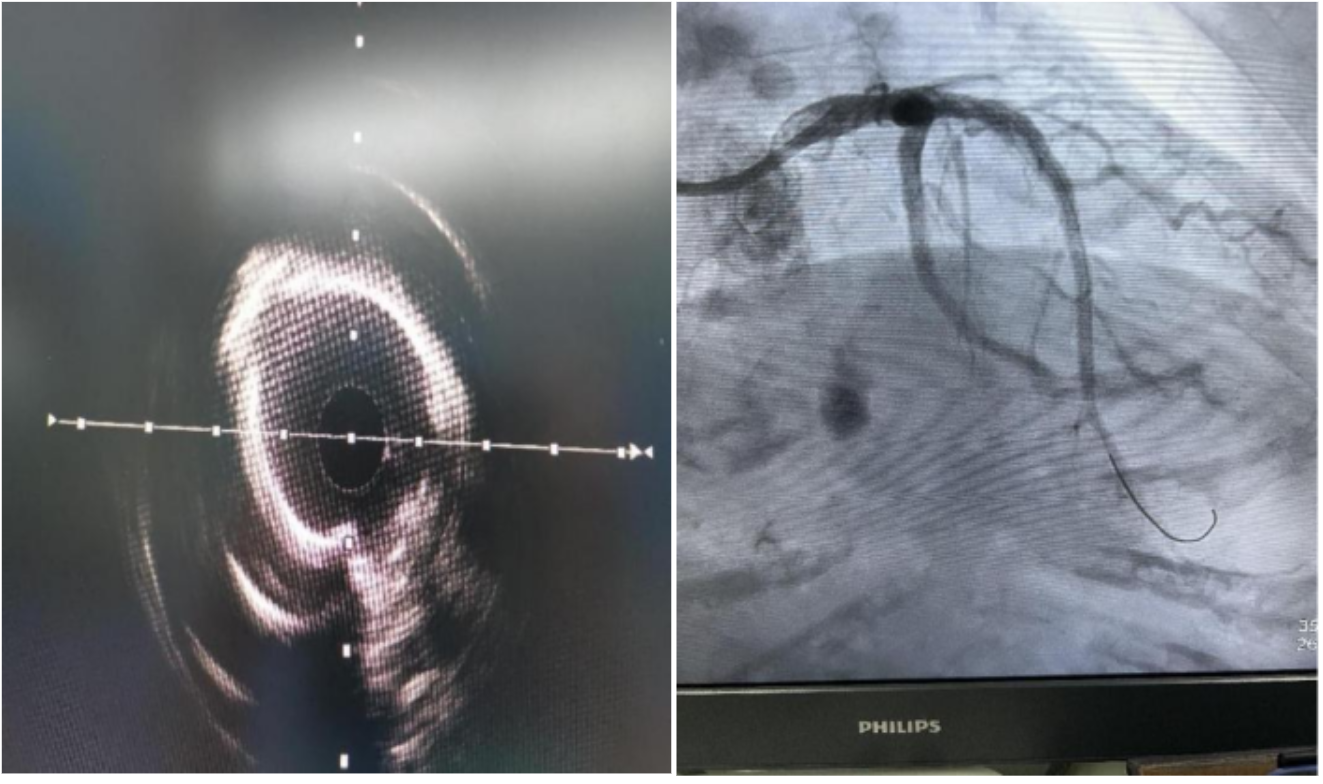

上图:冠脉造影及IVUS检查提示前降支重度狭窄伴严重钙化,普通球囊不能打开病变

上图:冲击波球囊及相关设备,经冲击波处理后冠脉钙化狭窄处扩张满意

患者李大娘今年77岁,反复胸闷胸痛多年了,过去10余年间,各种药吃了不少,但是最近病情突然加重,在家人的陪伴下她前往深圳市中医院就医。入院后,心血管病科明确诊断为急性非ST段抬高型心肌梗死,行冠脉造影检查示冠脉三支血管病变,最棘手的是前降支重度狭窄并严重钙化。

深圳市中医院心血管病科主任刘强表示:“患者的病变部位严重钙化,如果不尽快治疗,血管堵塞风险很高,甚至会有生命危险。”钙化病变属于高阻力病变,病变部位较硬,普通球囊难以通过,治疗难度比较大。